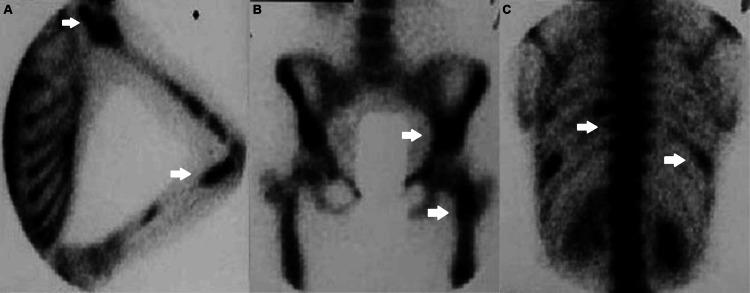

Mazabraud syndrome is a rare condition characterized by the coexistence of fibrous dysplasia (FD) and intramuscular myxomas. A 46-year-old woman, initially diagnosed with polyostotic FD at the age of 23, developed a palpable mass on her left arm 15 years later, which proved to be an intramuscular myxoma. A diagnosis of Mazabraud syndrome was made. Over the following two decades, she developed additional intramuscular myxomas. The patient denied surgical excision of the soft tissue lesions and was managed conservatively for symptomatic FD. Radiologic imaging, including MRI and ultrasound, played a crucial role in the diagnosis and the assessment of disease progression. Although both FD and myxomas are benign musculoskeletal abnormalities, close follow-up of the patients is essential to monitor changes in the number, distribution, and extent of lesions that may occasionally undergo malignant transformation. This case underscores the importance of early detection and long-term follow-up of patients with FD who may present with, or eventually develop, intramuscular myxomas, comprising Mazabraud syndrome.

马扎布劳德综合征是一种罕见疾病,其特征为骨纤维发育不良(FD)和肌内黏液瘤并存。一名46岁女性,23岁时最初被诊断为多骨型FD,15年后左手臂出现一个可触及的肿块,经证实为肌内黏液瘤。遂作出马扎布劳德综合征的诊断。在接下来的二十年里,她又出现了其他肌内黏液瘤。该患者拒绝手术切除软组织病变,对有症状的FD采取保守治疗。包括MRI和超声在内的放射学成像在疾病诊断和病情进展评估中发挥了关键作用。尽管FD和黏液瘤均为良性肌肉骨骼异常,但对患者进行密切随访对于监测可能偶尔发生恶变的病变的数量、分布和范围变化至关重要。该病例强调了对可能出现或最终发展为肌内黏液瘤(构成马扎布劳德综合征)的FD患者进行早期检测和长期随访的重要性。